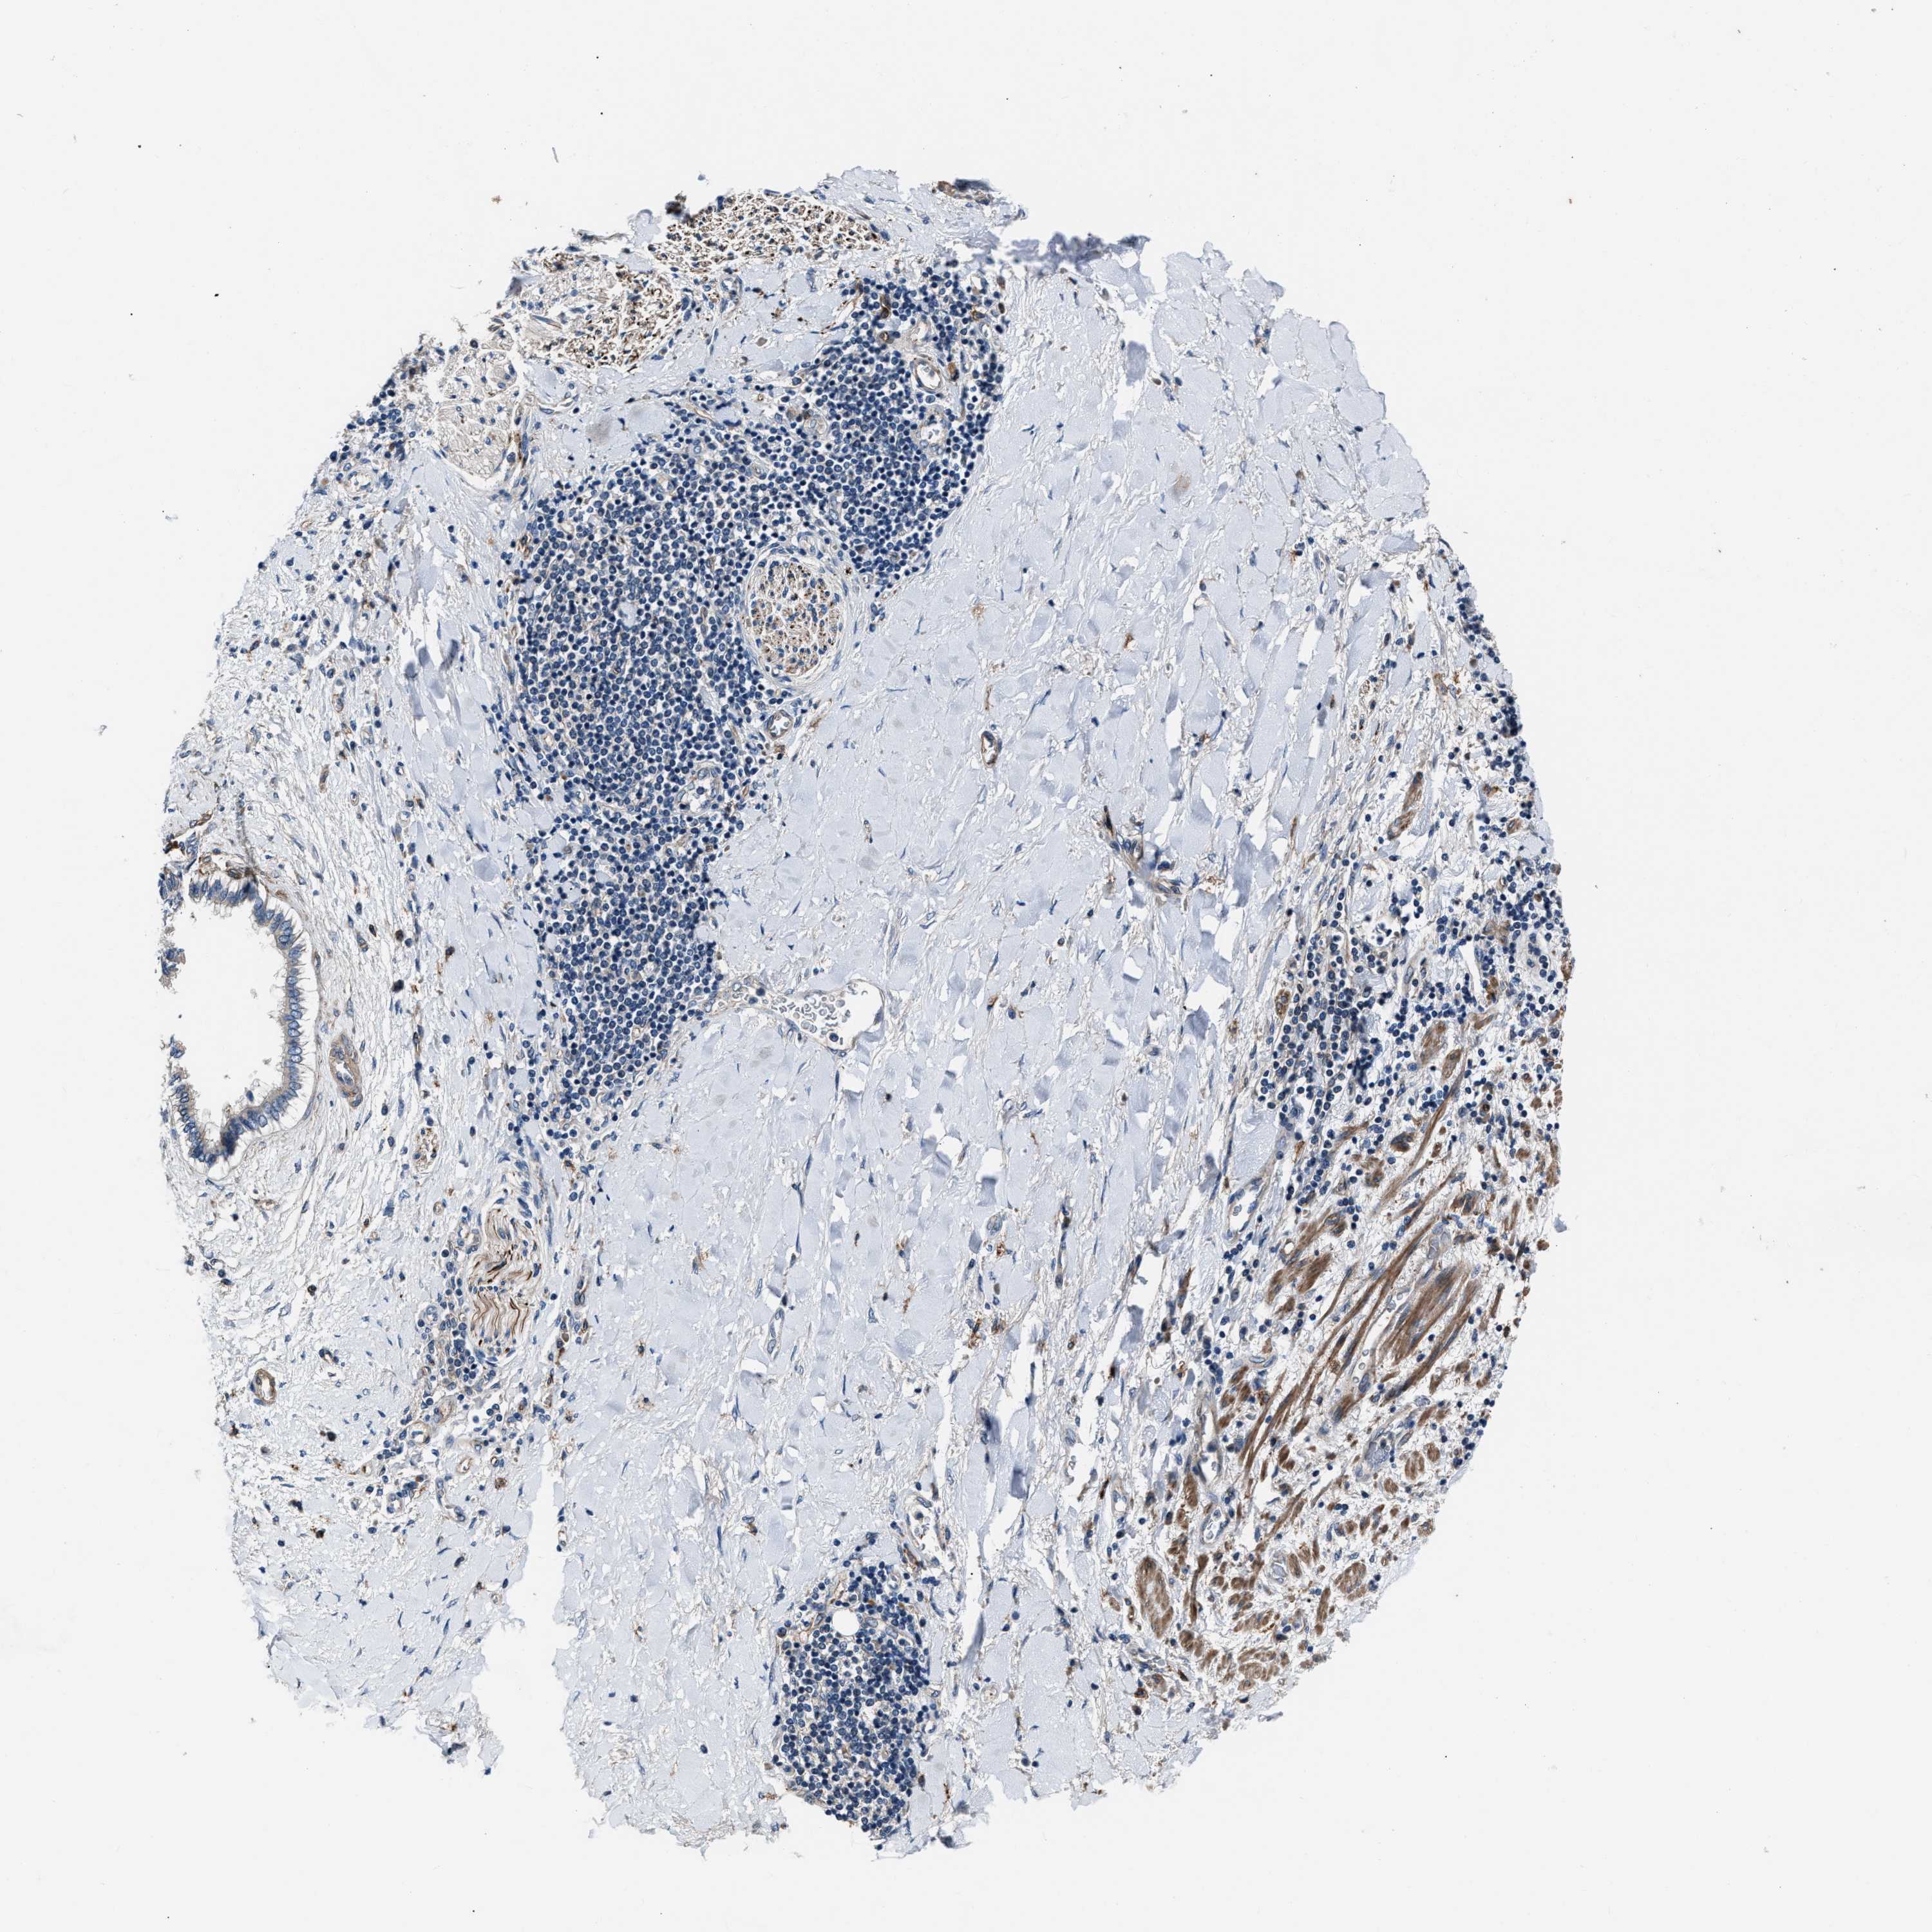

LIVER CANCER - Protein expressioni

A mouse-over function shows sample information and annotation data. Click on an image to view it in a full screen mode. Samples can be filtered based on level of antibody staining by selecting one or several of the following categories: high, medium, low and not detected. The assay and annotation is described here.

Note that samples used for immunohistochemistry by the Human Protein Atlas do not correspond to samples in the TCGA dataset.

Antibody stainingi

Antibody staining in the annotated cell types in the current human tissue is reported as not detected, low, medium, or high, based on conventional immunohistochemistry profiling in selected tissues. This score is based on the combination of the staining intensity and fraction of stained cells.

Each image is clickable and will lead to virtual microscopy that enables deeper exploration of all samples and also displays staining intensity scores, fraction scores and subcellular localization as well as patient and tissue information for each sample.

Antibody HPA020255

Antibody HPA026686

Antibody CAB013512

Staining

High

Medium

Low

Not detected

Intensity

Strong

Moderate

Weak

Negative

Quantity

>75%

75%-25%

<25%

None

Location

Nuclear

Cytoplasmic/membranous

Cytoplasmic/membranous,nuclear

Cholangiocarcinoma

Carcinoma, Hepatocellular, NOS